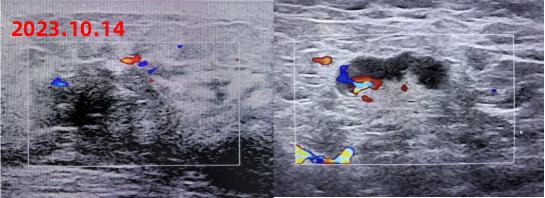

2023年10月14日 乳腺彩超

左侧低回声区,建议完善相关检查,BI-RADS 4A类

左腋下淋巴结肿大

图1 双侧乳腺及双腋下锁骨上下彩超

新辅助治疗后影像学复查结果如下:

疗效评价:PR